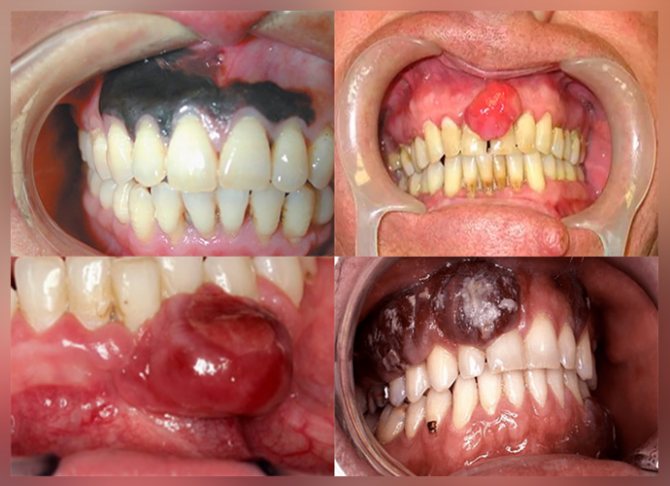

- Образование увеличивается до 1,5-2-х см в диаметре и становится багрово-красным. На этой стадии рак может прорасти в челюстную кость, но метастазов еще нет. Это затрудняет определение того факта, что развивается онкология.

- Прогрессирующее разрастание раковой ткани охватывает всю полость рта и начинает распространяться в другие органы. В первую очередь – в регионарные лимфатические узлы: подчелюстные, около- и заушные.

- Нарост на десне увеличен до больших размеров (диаметром более 3 см). Метастазирование происходит в жизненно важные органы человека (печень, органы дыхания).

Чем больше стадия развития новообразования, тем легче поставить правильный диагноз, но тяжелее прогноз. На 4-й стадии излечение невозможно.

Без лечения рак десны стремительно прогрессирует, поражая окружающие мягкие ткани, хрящевые и костные структуры, нервные сплетения. Опухоль десен способна стимулировать образование новых кровеносных сосудов, чтобы обеспечить себе достаточное питание. По этим сосудам раковые клетки распространяются по организму, формируя очаги метастазирования.

Злокачественная опухоль для своего роста требует притока большого объема крови и провоцирует увеличение количества мелких кровеносных сосудов на участке поражения. Поэтому рак десен выглядит как красноватый участок, а при малейшем механическом воздействии на нем появляется кровоточивость.

Злокачественная опухоль подразделяется на три формы, в зависимости от того, как выглядит рак десен:

- Язвенная – выглядит как изъявление слизистой оболочки, имеющее неровные края, кровоточащее при прикосновении.

- Папилломатозная (сосочковая) – представляет собой бугорок с неровными краями, внешне может выглядеть, как головка цветной капусты.

- Инфильтративная – глубокое поражение, не имеющее четких границ.

Первые признаки рака десен на 3 и 4 стадии

Рак десен на 3 стадии характеризуется увеличением новообразования в размерах и вовлечением окружающих тканей в патологический процесс. Уже имеющиеся симптомы рака десны усиливаются – наблюдаются значительные изменения слизистого эпителия, глубокие эрозии, постоянная кровоточивость и острые боли.

Признаки рака десен на поздних стадиях:

Рак верхней десны способен распространяться в полость носа и носовые пазухи, от чего появляется постоянная заложенность носа, обильные слизистые выделения с вкраплениями крови. Если опухоль десен прорастает в основание черепа, появляются стойкие зрительные и неврологические нарушения.